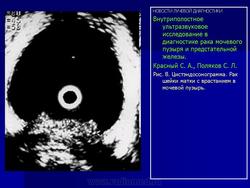

Внутриполостное ультразвуковое исследование в диагностике рака мочевого пузыря и предстательной железы.

Красный С. А., Поляков С. Л.

Эндовезикальное сканирование позволяет дифференцировать все слои мочевого пузыря (Рис. 1). Между мышечной стенкой и слизистой оболочкой визуализируется гипоэхогенная подслизистая соединительная ткань. При стадии рака мочевого пузыря Та (инвазия в пределах слизистой) создается впечатление, что опухоль отделена от мышечной стенки мочевого пузыря, то есть подслизистый слой остается неизмененным (Рис. 2), также хорошо визуализируются устья мочеточников. При распространении инвазии субэпителиальной соединительной ткани (стадия Т1) опухоль уже непосредственно прилежит к мышечному слою, но не инвазирует последний (Рис. 3).